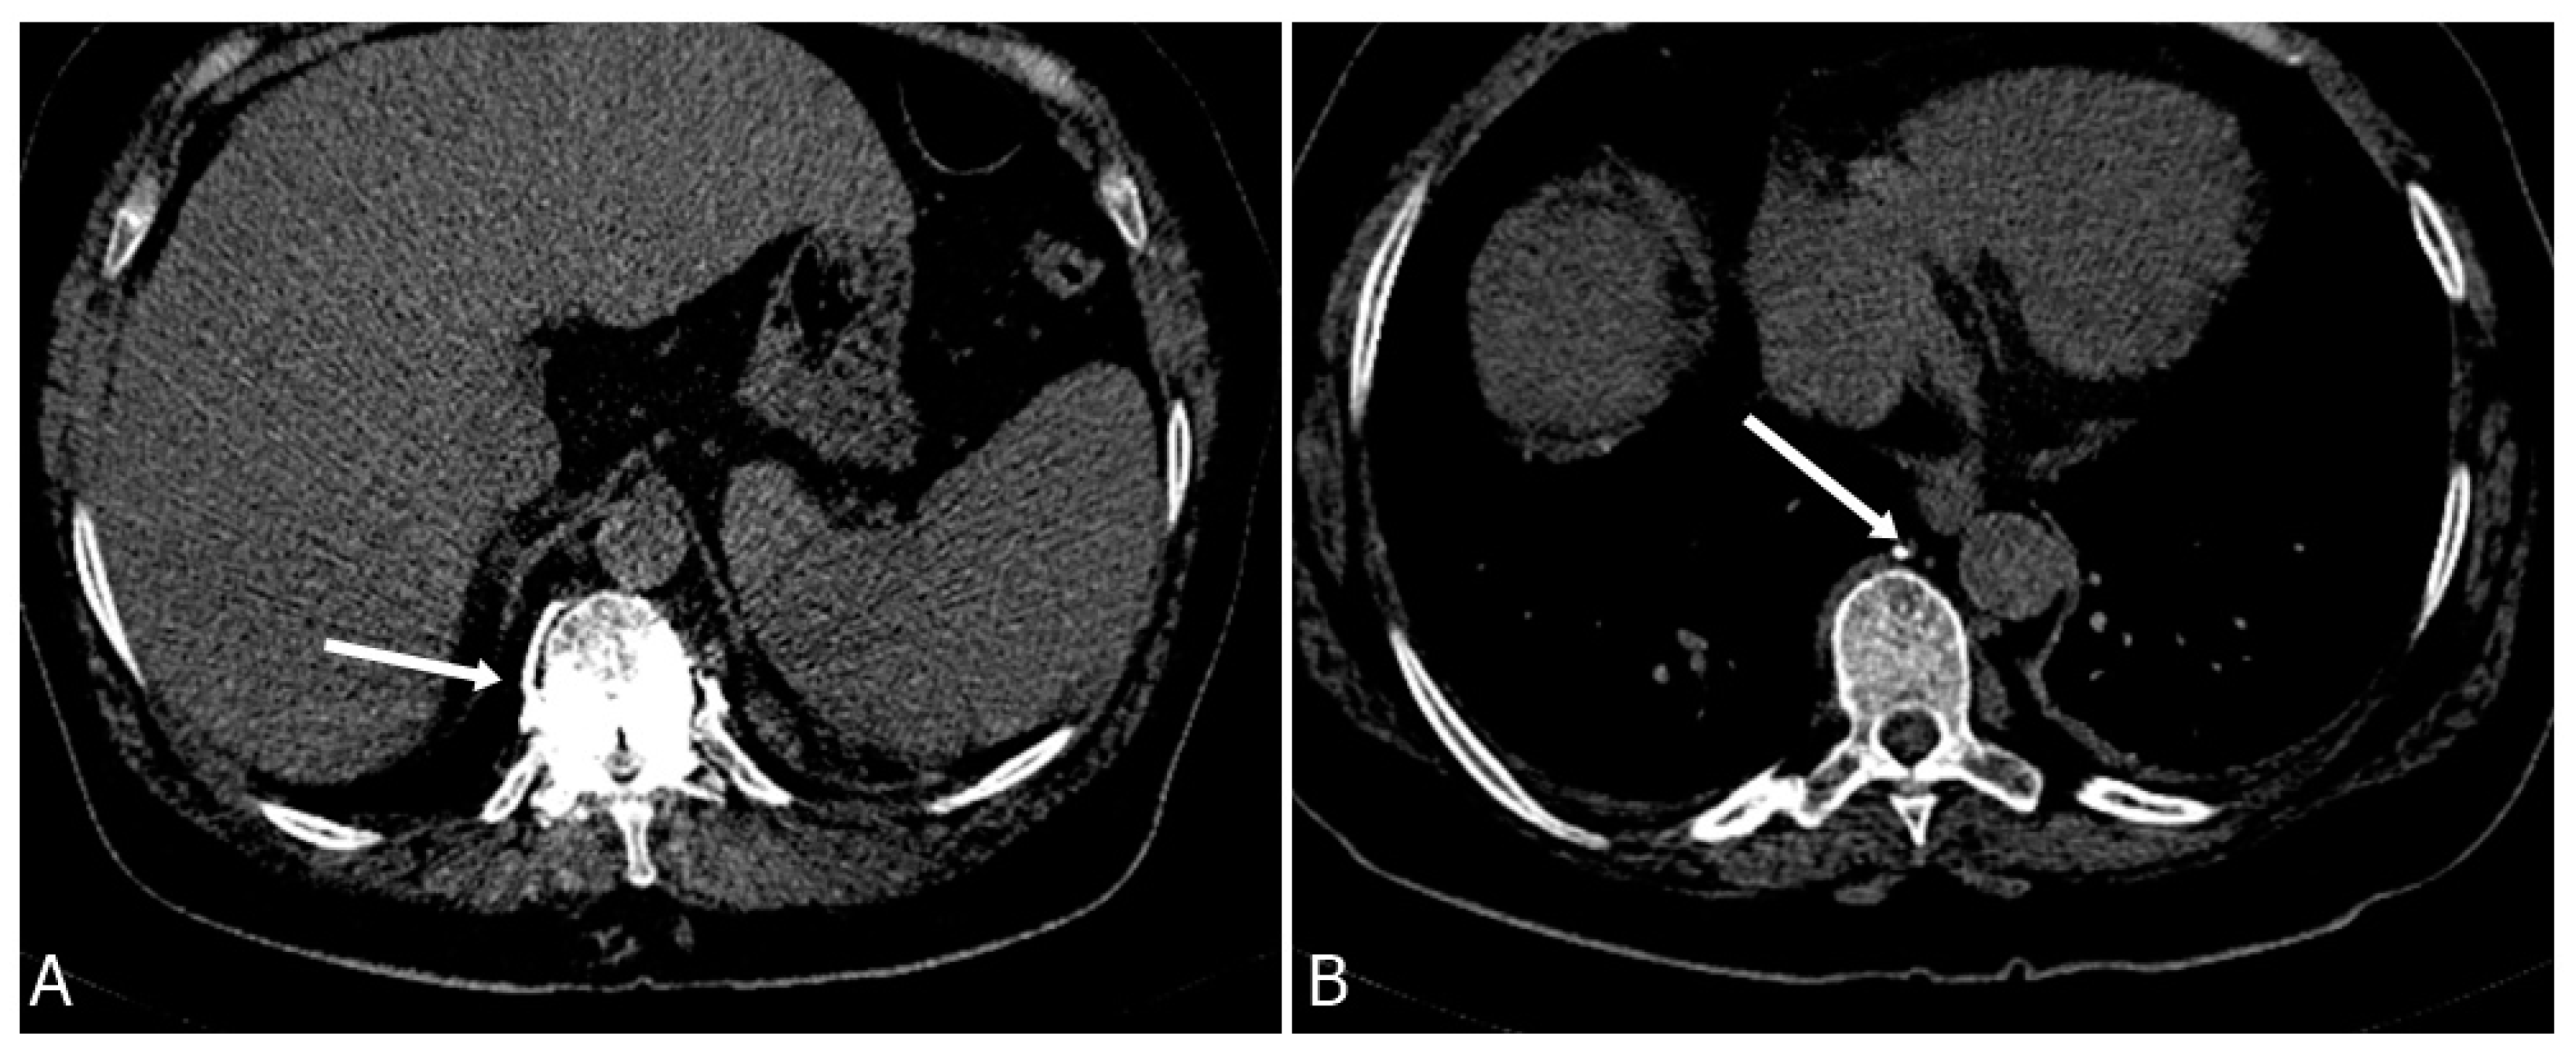

3.4. Venous System Cement Leakage and Pulmonary Embolism